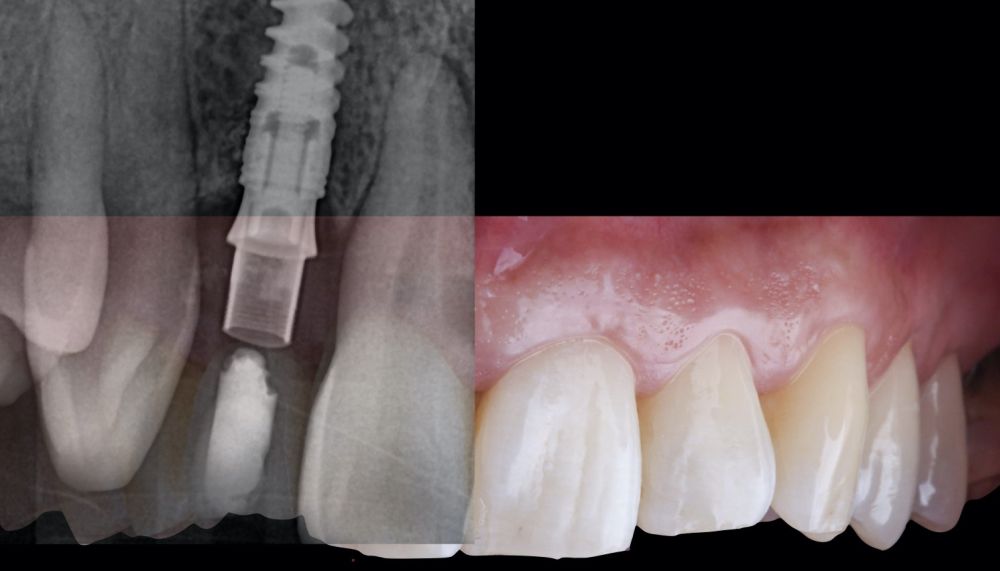

-Fase II: la cicatrización transcurrió sin complicaciones. Tras 5 meses de la cirugía de preservación alveolar, se planificó la cirugía implantológica guiada en posición 1.2 (Figura 2). Para ello, se utilizaron un archivo DICOM procedente de la tomografía computarizada de haz cónico (CBCT) y el archivo STL procedente del escaneado mediante un escáner óptico intraoral. Con esta información se construyó una férula quirúrgica de soporte dental (Figura 3). La férula quirúrgica se ancló sobre los dientes y guió la realización del lecho implantario y la colocación del implante. La técnica quirúrgica de cirugía guiada consistió en una cirugía con colgajo, preparando e insertando el implante (3,5 x 11,5 mm) según el protocolo estandarizado de cirugía guiada Nobel Active® (Nobel Biocare AB, Gothenburg, Sweden). Una vez colocado el implante 1.2, se obtuvo un injerto gingival compuesto de epitelio y tejido conectivo de la mucosa masticatoria palatina. A continuación, se realizó la desepitelización de la capa superficial de dicho injerto fuera de boca mediante una hoja de bisturí 15C con la finalidad de obtener un injerto de tejido conectivo de la capa subyacente18.

-Fase III: tres meses tras la colocación del implante, la situación del tejido blando era favorable (Figuras 5 y 6). Se tomó una impresión digital mediante escáner intraoral para la realización de un provisional atornillado de polimetilmetacrilato (PMMA). Respecto a la corona implantaria definitiva se realizó una restauración cemento-atornillada con una interfase de titanio nitrurado adaptando el diseño al perfil de emergencia ya consolidado con la prótesis provisional. La corona se realizó por CAD-CAM en zirconio con reducción completa y estratificación de cerámica feldespática de recubrimiento para zirconio (Figura 7).

El resultado clínico final fue satisfactorio cumpliendo las demandas estéticas del paciente. Los tejidos blandos estaban morfológicamente y dimensionalmente estables sin ningún signo de inflamación. Sin embargo, los cambios del tejido blando periimplantario (espesor volumétrico vestibular) fueron demostrados de manera cualitativa y cuantitativa (Figuras 8 y 9). En el postoperatorio inmediato (T1), la ganancia media obtenida al comparar T0 frente a T1 fue de 0,88 ± 0,15 mm con un incremento máximo de 1,1 mm. Al comparar T0–T2, se observó una ganancia media de 0,73 ± 0,23 mm. Es decir, se ha producido una contracción de volumen de 0,16 mm desde la colocación del injerto (T1) hasta pasado un mes y medio (T2).